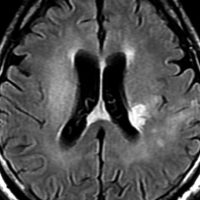

MRI画像所見 60代で嚥下障害と構音障害で発症した例

延髄から中脳まで腫瘍があって脳幹部が腫れています。この画像ですと,小児のびまん性橋膠腫(DIPG,びまん性正中グリオーマ)のように見えます

両側視床から大脳基底核,両側大脳半球深部白質,脳梁まで広範囲に腫瘍が存在します。退形成性星細胞腫のようにまだらにガドリニウム増強されます。